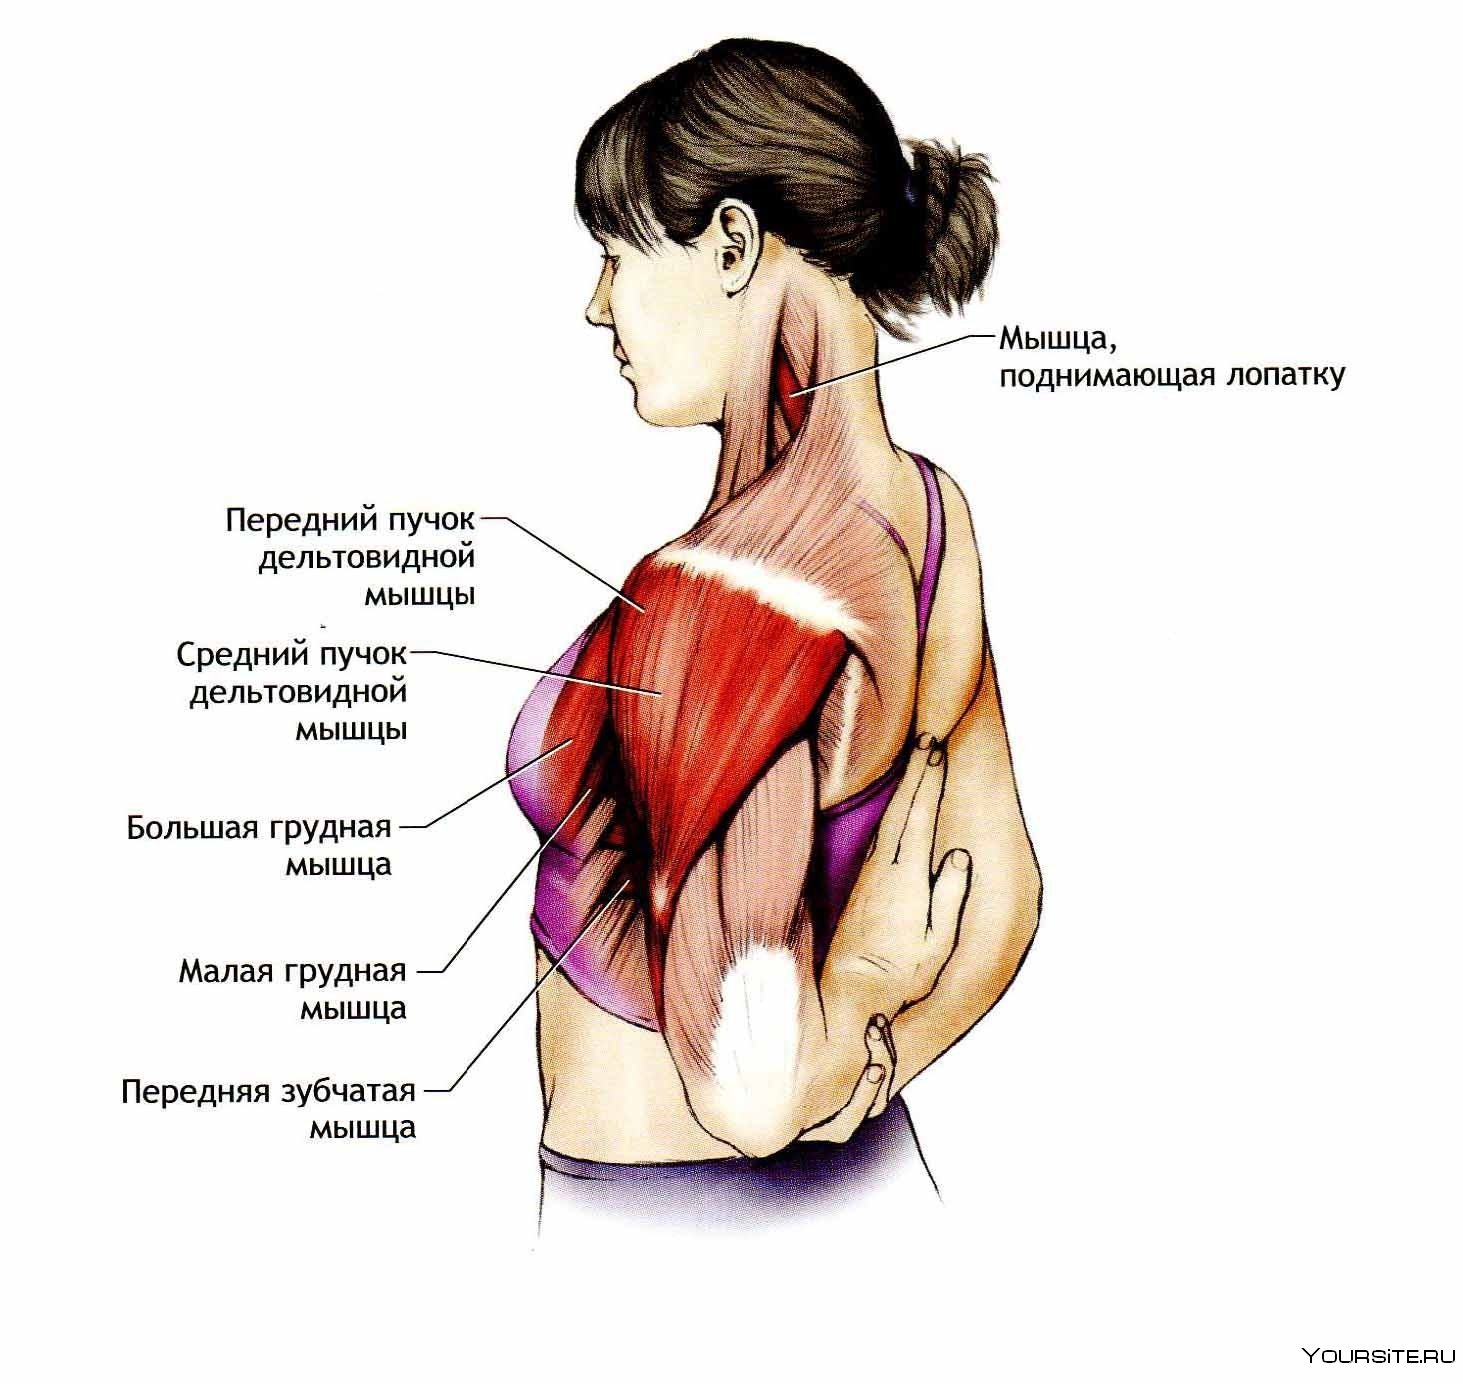

Фотографии поддельтовидной мышцы плечевого сустава